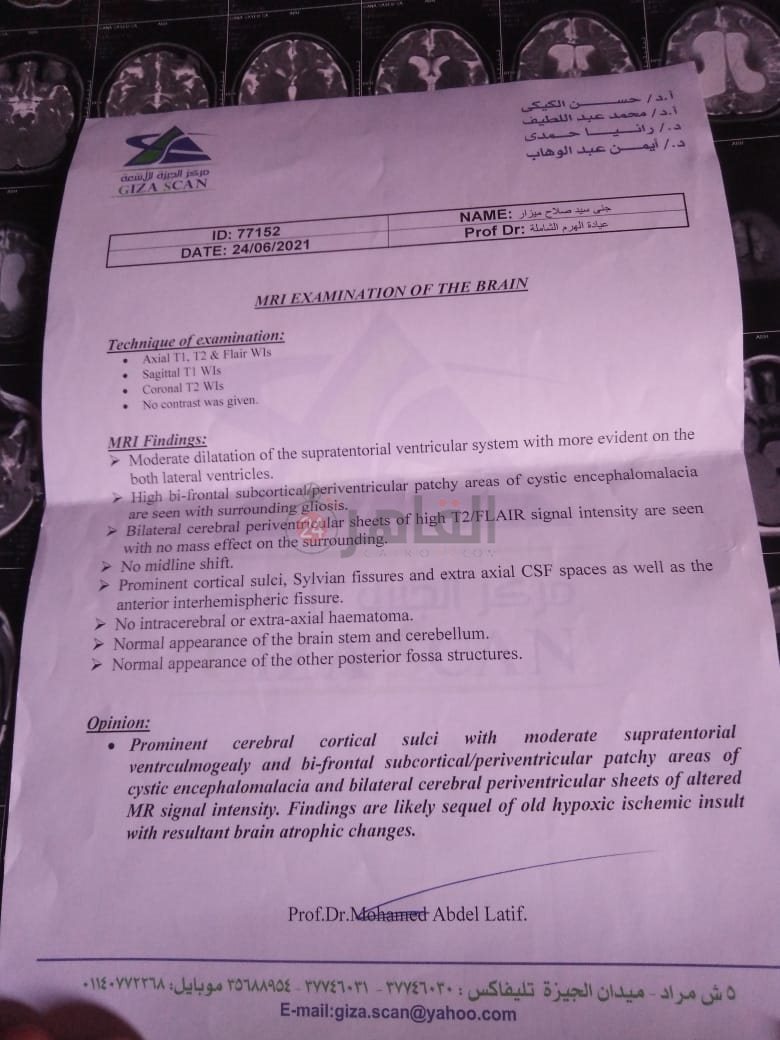

من جانبه، قال صلاح سيد، والد الطفلة جنى صلاح، إن ابنته تعاني من ضمور في المخ منذ ولادتها، نتيجة خطأ طبي، أدى إلى نقص كبير في الأكسجين لديها.

وأضاف في تصريحات خاصة لـ "القاهرة 24": "جنى تبلغ من العمر 6 سنوات، لا تستطيع المشي أو الوقوف على قدميها، نتيجة إصابتها بضمور في المخ منذ ولادتها".

وتابع: "مكنتش بتتحرك خالص، وجسمها طري، روحت كشفت عليها، وعملت أشعة وتحاليل كتير، أتأكدنا إصابتها بضمور في المخ"، مضيفًا:" مش بتعرف تأكل احنا اللي بنأكلها، هي عقلها كويس لكن مش بتتحرك ولا تتكلم".

وأوضح أن الطبيب الخاص بها أكد أن هناك داء خارج مصر يحسن من حالتها، ولكن باهظ الثمن، وتحتاج تناوله بشكل دوري.

واستكمل:" حاليًا تتناول أدوية شرب عادية، لحين توفيرالدولة علاجها من خارج مصر"، مشيرًا: "مفعتش قضية على الدكتور، ورضيت بقضاء ربنا".